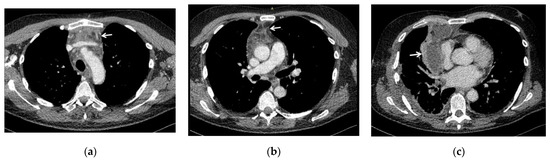

In all 15 cases it was necessary to combine a thoracotomy with a cervicotomy to obtain a complete cervical, mediastinal and pleural drainage (Figure 2); in particular, one patient underwent cervicotomy extended to pectoralis major and pectoralis minor muscles because there was a spread of the infective process also at this site; in two cases with odontogenic origin of the infection, treatment of the abscess of the diseased tooth was also carried out.

Figure 2. In all cases, mediastinum drainage via thoracotomy was performed after neck drainage via cervicotomy: (a) intra-operative field during cervicotomy showing purulent material (white arrow) coming from the cervical fasciae; (b) intra-operative field during thoracotomy, showing yellowish purulent collection (white arrow) in the anterior mediastinum (the lung has been retracted).